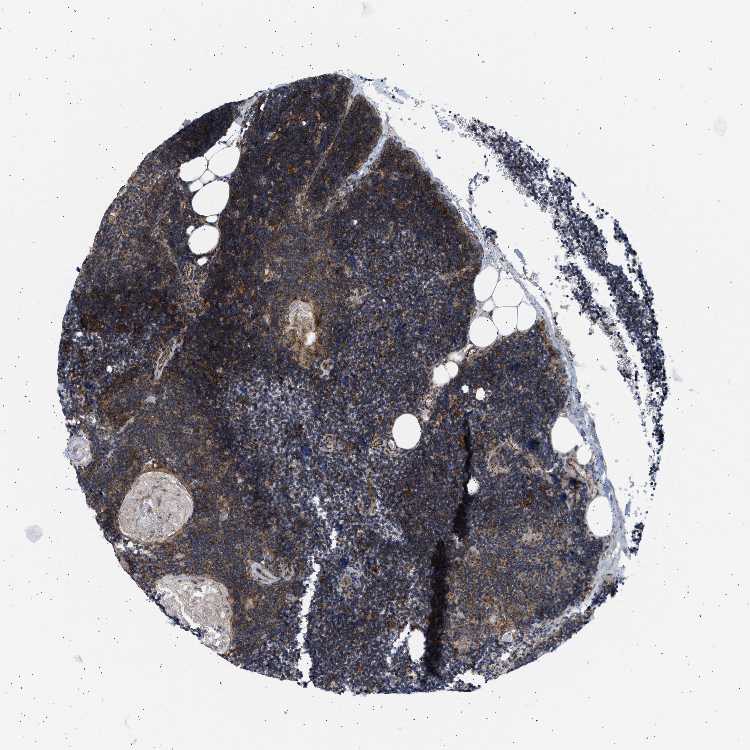

TISSUE PRIMARY DATA LYMPH NODE Show tissue menu

Lymph node

LYMPH NODE - Antibody stainingi

Antibody staining in the annotated cell types in the current human tissue is reported as not detected, low, medium, or high, based on conventional immunohistochemistry profiling in selected tissues. This score is based on the combination of the staining intensity and fraction of stained cells.

Each image is clickable and will lead to virtual microscopy that enables deeper exploration of all samples and also displays staining intensity scores, fraction scores and subcellular localization as well as patient and tissue information for each sample.

Antibody HPA038026Antibody CAB017532

Germinal center cells Not detectedMedium

Non-germinal center cells Not detectedMedium